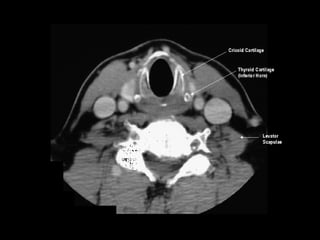

Radiographers use medical imaging equipment like X-rays and MRIs to produce images of patients' internal structures and organs. They are responsible for positioning patients, operating scanning machines, and ensuring quality images. Radiographers must have strong attention to detail, excellent communication skills, and the ability to work well under pressure to accurately capture anatomical features and diagnose any abnormalities.